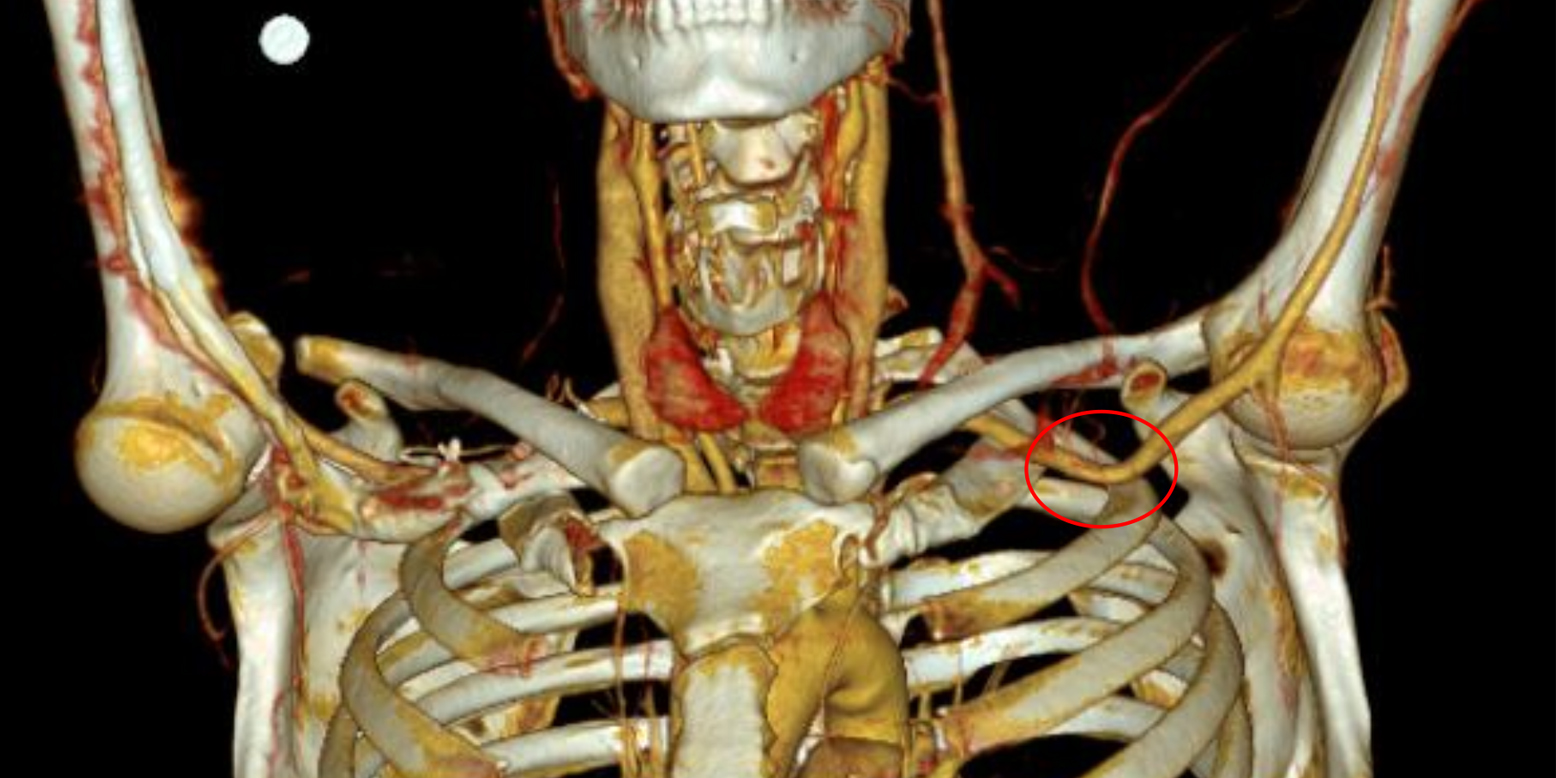

Schauen wir auf die Abbildungen 2.1. – 2.5.: Die Diagnostik der Endofibrose umfasst eine Ruhe- und Belastungstestung der Knöchel-Arm-Indizes (ABI; ankle-brachial-index) mit segmentaler Puls-Oszillographie (Symbolbilder 2.1 und 2.2, nicht der Athlet vom Fall 2), eine Duplexsonographie (B-Flow Modus, Bild 2.3.), sowie eine MR-Angiographie (dezente Lumeneinengung mit rotem Pfeil, Bild 2.4.), wobei die Tunica Intima-Media-Verdickung, welche sich in 90 % der Fälle im Bereich der A. iliaca externa (Schema-Zeichnung mit rotem Pfeil, Bild 2.5.) befindet, herausgearbeitet werden kann.

Dieser Fall repräsentiert eine typische Beschwerdesymptomatik im Sinne einer Endofibrose der Beckenarterien (oder FLIA; flow limitation of iliac arteries). Differenzialdiagnostisch sollte hierbei eine Pathologie des Iliosakralgelenkes, eine dynamische Spondylolisthese sowie ein femoroazetabuläres Impingement ausgeschlossen werden. In seltenen Fällen kann sich auch ein Entrapment der kutanen Äste des N. femoralis ähnlich manifestieren. Im vorliegenden Fall konnte jedoch der hochgradige Verdacht einer Endofibrose der Arteria iliaca externa auch in der Magnetresonanzangiographie bestätigt werden. Wichtig ist die Abgrenzung der Endofibrose (= Verdickung der inneren und mittleren Gefäßwandschicht an der großen Gefäßkurvatur) von der peripheren arteriellen Verschlusskrankheit, bzw. der Arteriosklerose (= Plaqueatheromatose an der kleinen Gefäßkurvatur). In einem Kollektiv von Leistungssportlern beziffert sich die geschätzte Prävalenz der Endofibrose / FLIA auf rund 10 – 20 % [3]. Dabei sind Straßenrennradfahrer und Triathleten, welche sich häufig über längere Zeit in der aerodynamisch Position befinden, häufiger betroffen als Mountainbiker. Dies liegt wohl primär an der Geometrie der Arterie unter Belastung, wobei es etwa 2 – 6 cm nach Abgang der Arteria iliaca interna zu einer Knickbildung des A. iliaca externa kommt und aufgrund der rund 4-6-fach erhöhten Herzminutenvolumen auch entsprechende Scherkräfte im Bereich der Tunica intima / media der Gefäßwand entstehen können. Radfahrer genießen jedoch diesbezüglich keine Exklusivität. Auch Eisschnellläufer, Marathonläufer oder Ruderer können an Endofibrose erkranken. Als weitere prädisponierende Faktoren für die Entstehung eines Kompressionssyndroms ebendort sind auch die Hypertrophie des Musculus psoas major, nutritive Arterien von der Beckenarterie zum Psoas, sowie eine Elongation des Gefäßes mit assoziiertem „Kinking“ (Knickbildung insb. bei Hüftflexion) zu nennen [4]. In Bezug auf die Therapie sind konservative Maßnahmen, wie die Optimierung der Lenker-/Sattel-/Pedalen-Position („Bikefitting“), die vermehrte Kraftübertragung auf die Pedalen via Glutealmuskulatur, oder auch die Optimierung des Stickstoffhaushaltes am Endothel mittels Folsäure-Substitution nur selten erfolgreich. Goldstandard hier ist somit ebenfalls die offen-gefäßchirurgische Sanierung mittels Längsarteriotomie und venöser Patch-Plastik. Von einer endovaskulären Stent-Implantation sollte bei dieser Entität aufgrund der Gefahr von Stent-Frakturen bei anhaltender sportlicher Belastung dringend abgeraten werden.